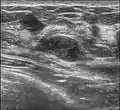

Fibroadenoma in ultrasound